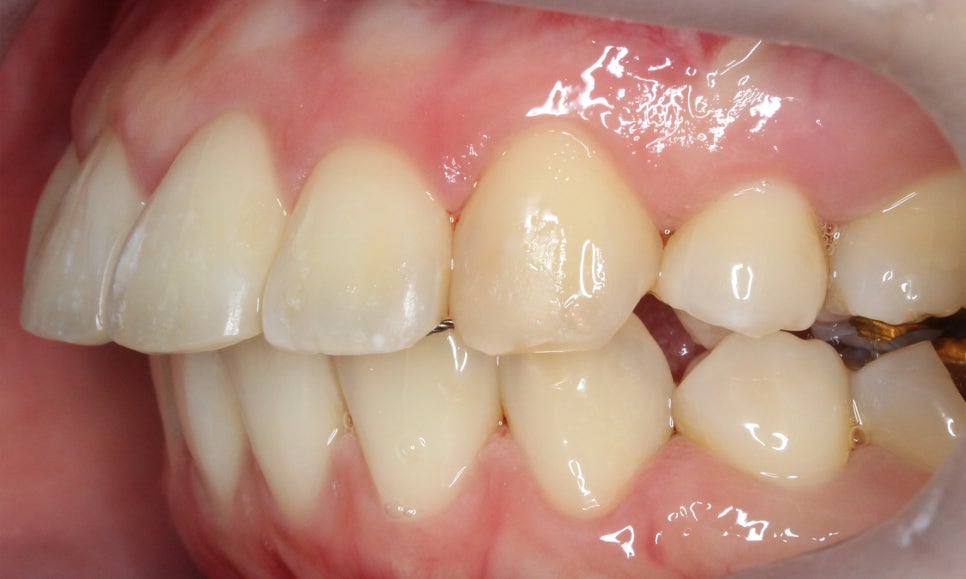

측면에서 치아의 돌출감을 살펴보면

상악 교정 후 중절치가 튀어나온 증상이

크게 완화된 모습인데요,

비발치 교정이기 때문에

완전하게 돌출감이 사라지지는 않았지만

스마일라인이 어색하지 않도록

자연스럽게 돌출감을 교정한 모습입니다.

좌우 교합 평면 사진에서도

클리피씨교정을 끝내 상악이

하악에 비해 비교적 가지런하게

배열된 모습으로

중절치의 각도가 특히

바르게 바뀐 모습입니다.